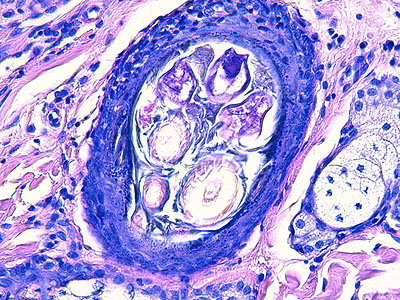

Photo 5 : (Hémalun-Eosine – X400) : Vue rapprochée d’un isthme folliculaire,

permettant de visualiser la plurilobulation “médusoïde” d’une glande sébacée,

l’hyperplasie et l’hyperkératose orthokératosique de son canal excréteur et

l’inflammation péri-isthmique lympho-plasmocytaire.

Légendes de la Photo 5 :

- Pointe de flèche rouge = lumière du canal sébacé hyperkératosique

- Étoile turquoise = paroi épithéliale hyperplasique du canal sébacé

- Carré rouge = lumière del’isthme follicualire

- Étoile rouge = lobules d’une glande sébacée hyperplasique

- Étoile rouge = infiltrat inflammatoire lympho-plasmocytaire péri-isthmique, le reste du derme n’est pas inflammatoire